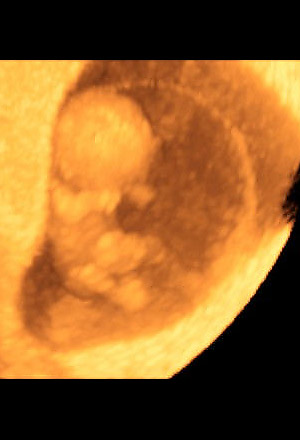

| | 3 / 12 Month 2 (Week 8)

At 8 weeks, the embryo is now almost 25 mm (1 inch) long with a head, arms, legs and a tail. The organ systems -- kidneys, brains and eyes -- are developing. Ears are forming and even the tip of the nose is visible. The arms and legs are well formed. The fingers and toes become more distinct.